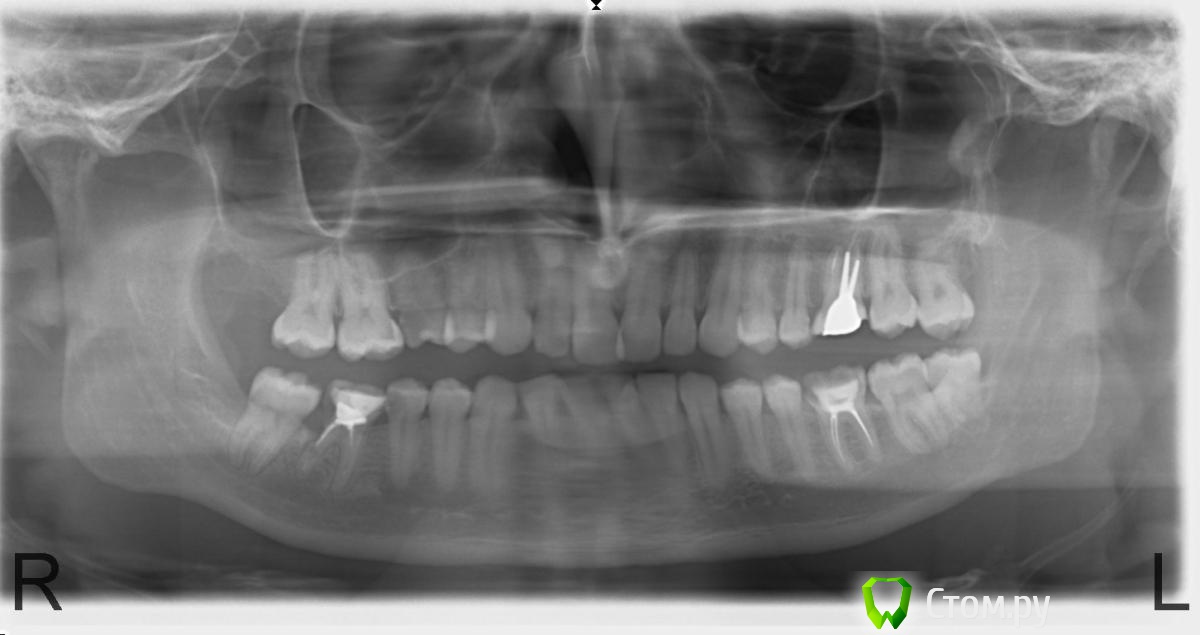

max2141 Опубликовано 6 февраля, 2014 Поделиться Опубликовано 6 февраля, 2014 Здравствуйте! Подскажите, насколько травматичным будет удаление 48 зуба (надо ли спиливать кость) и примерный период восстановления после удаления. Снимок прилагаю.Спасибо! Ссылка на комментарий

IvanK Опубликовано 6 февраля, 2014 Поделиться Опубликовано 6 февраля, 2014 Здравствуйте, насколько травматичным будет удаление 48 зуба в умелых руках - не травматично,ищите Врача, для которого данное удаление - рутина. период восстановления как после обычного удаления, возможен отекСоветовал бы удалить все 8ки, _+ 46консультация ортодонтаповторное лечение с последующим протезированием коронками 26,36 3 Ссылка на комментарий

IvanK Опубликовано 6 февраля, 2014 Поделиться Опубликовано 6 февраля, 2014 26 лечил только в декабре тогда давайте новый снимок 46 мне предлагали лечить заново каналы и ставить коронку, судя по снимку пол корня там уже нет 1 Ссылка на комментарий

max2141 Опубликовано 29 мая, 2014 Автор Поделиться Опубликовано 29 мая, 2014 Добрый день, уважаемые доктора! Беспокоят периодические боли в области 26 зуба, врач советует подождать. Хотелось бы услышать ваше мнение.Также интересно, что удалять раньше: 46 или восьмёрки? Заранее благодарю! Ссылка на комментарий

faity Опубликовано 29 мая, 2014 Поделиться Опубликовано 29 мая, 2014 я бы с 4.6 начал, пока кость подживет- уберете восьмерки, уберете восьмерки тут и до имплантации недолго 1 Ссылка на комментарий